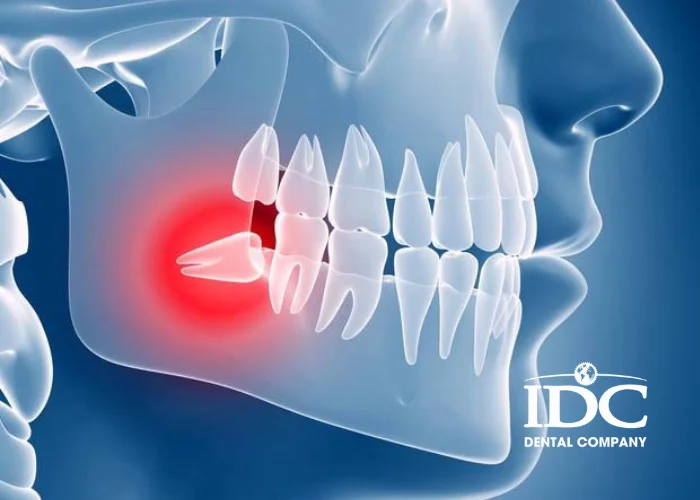

Wisdom teeth (tooth number 8) are the last teeth to grow in the jaw, usually appearing between 17–25 years old. Because of limited space, wisdom teeth are very likely to grow crooked, become impacted, cause swelling and pain, damage nearby teeth, inflamed gums, and other serious complications. Extracting wisdom teeth is the safest and most effective way to prevent infection and protect long-term oral health.

Wisdom tooth is misaligned and pushing against tooth number 7

• Impacted wisdom tooth,

• pressing on nerves, causing radiating tingling